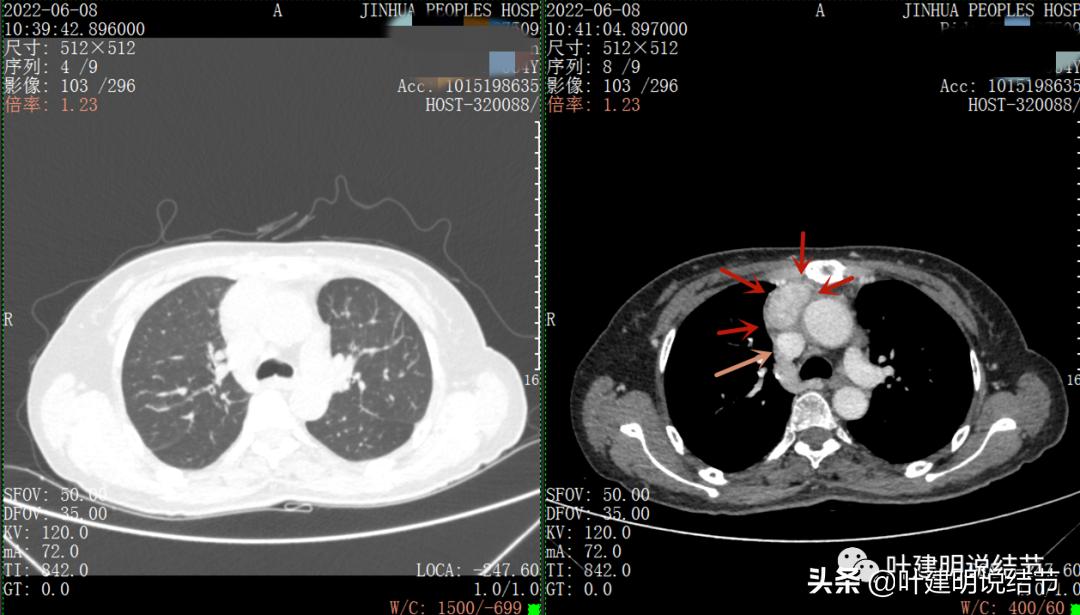

以下图片左侧是肺窗,右侧是纵隔窗。红色箭头示病灶,桔色箭头示无名静脉,黄色箭头示支气管,砖色箭头示上腔静脉,蓝色箭头示主动脉,紫色箭头示肺动脉。

病灶胸顶较高位置就出现了,在无名静脉水平

无名静脉略受压